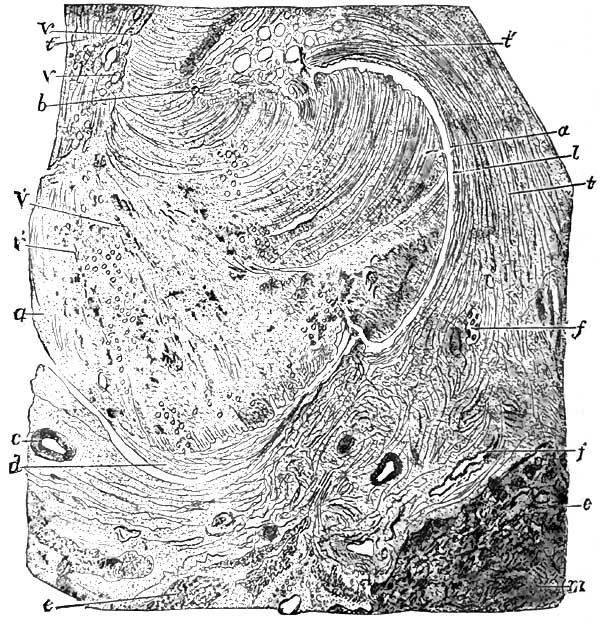

| 8. | SECTION OF AN OLD GUMMA OF THE LIVER |

| 9. | SYPHILITIC DACTYLITIS, FROM BUMSTEAD |

| 10. | THE SAME AS FIG. 9 |